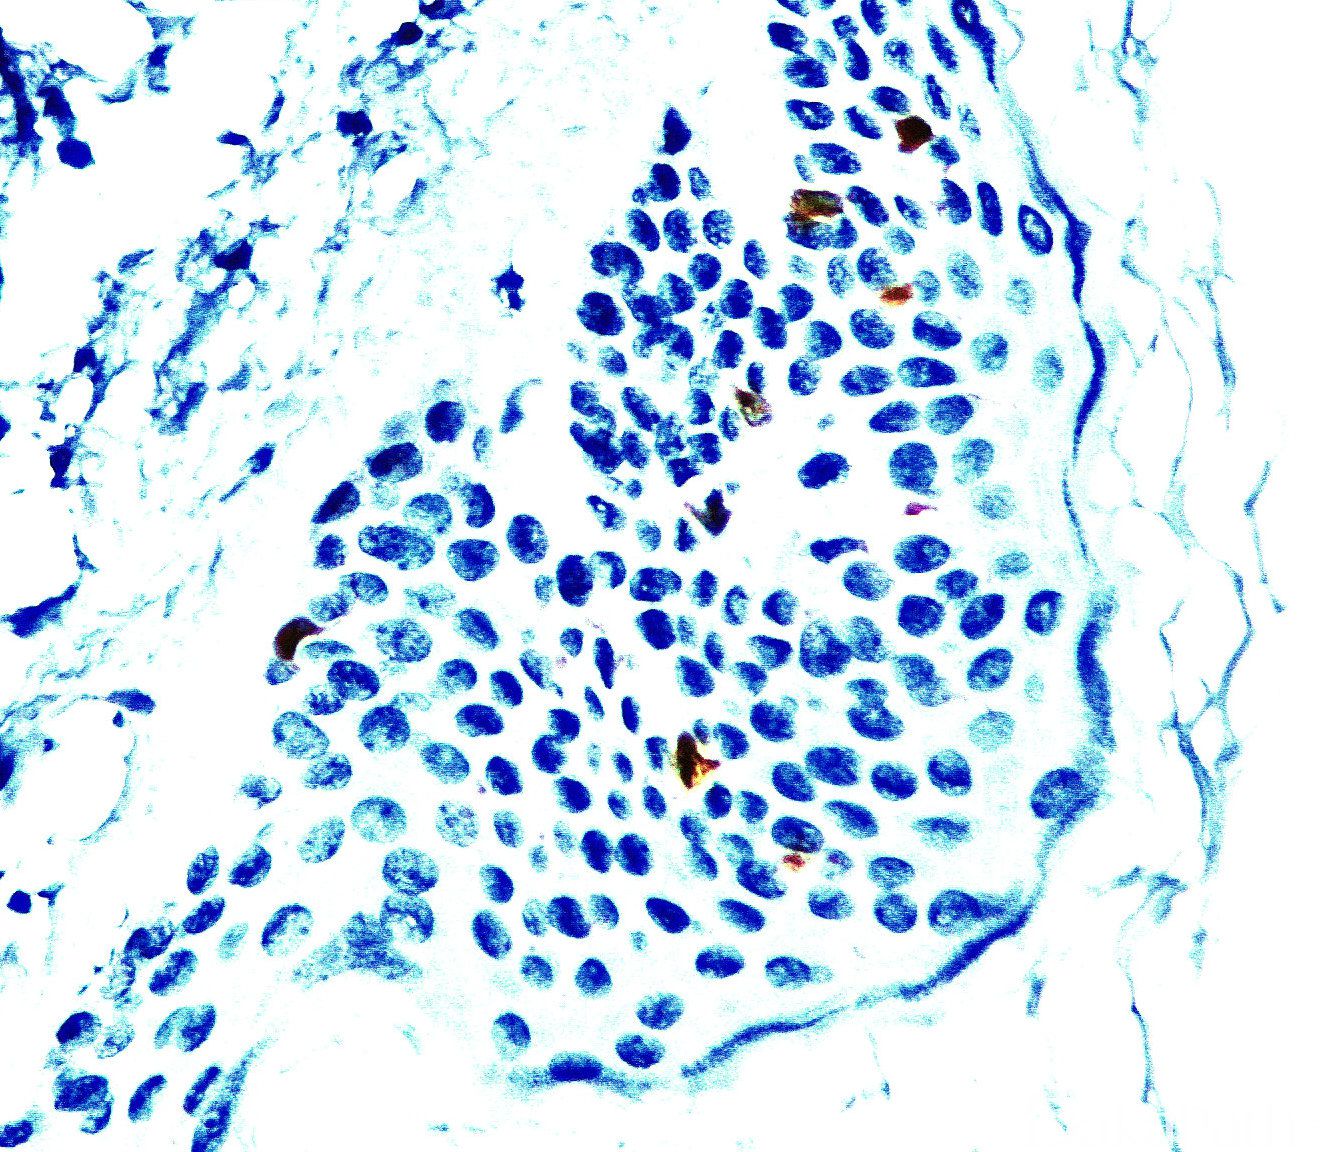

肺朗格汉斯细胞组织细胞增生症和肺外朗格汉斯细胞肉芽肿的诊断;

有时阳性(<55%,≥35%的病例阳性): 组织细胞/树突状细胞肉瘤